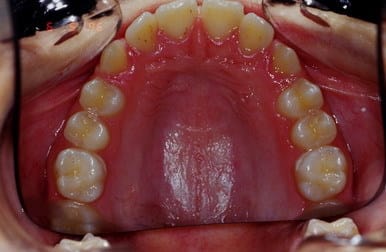

Cas 1 suite

5 rgkioo - Eugenol

6 ju9t9x - Eugenol

7 grbeiz - Eugenol

cas 1 suite et fin

Noter la fermeture des diastemes infer. sans aucune mecanique